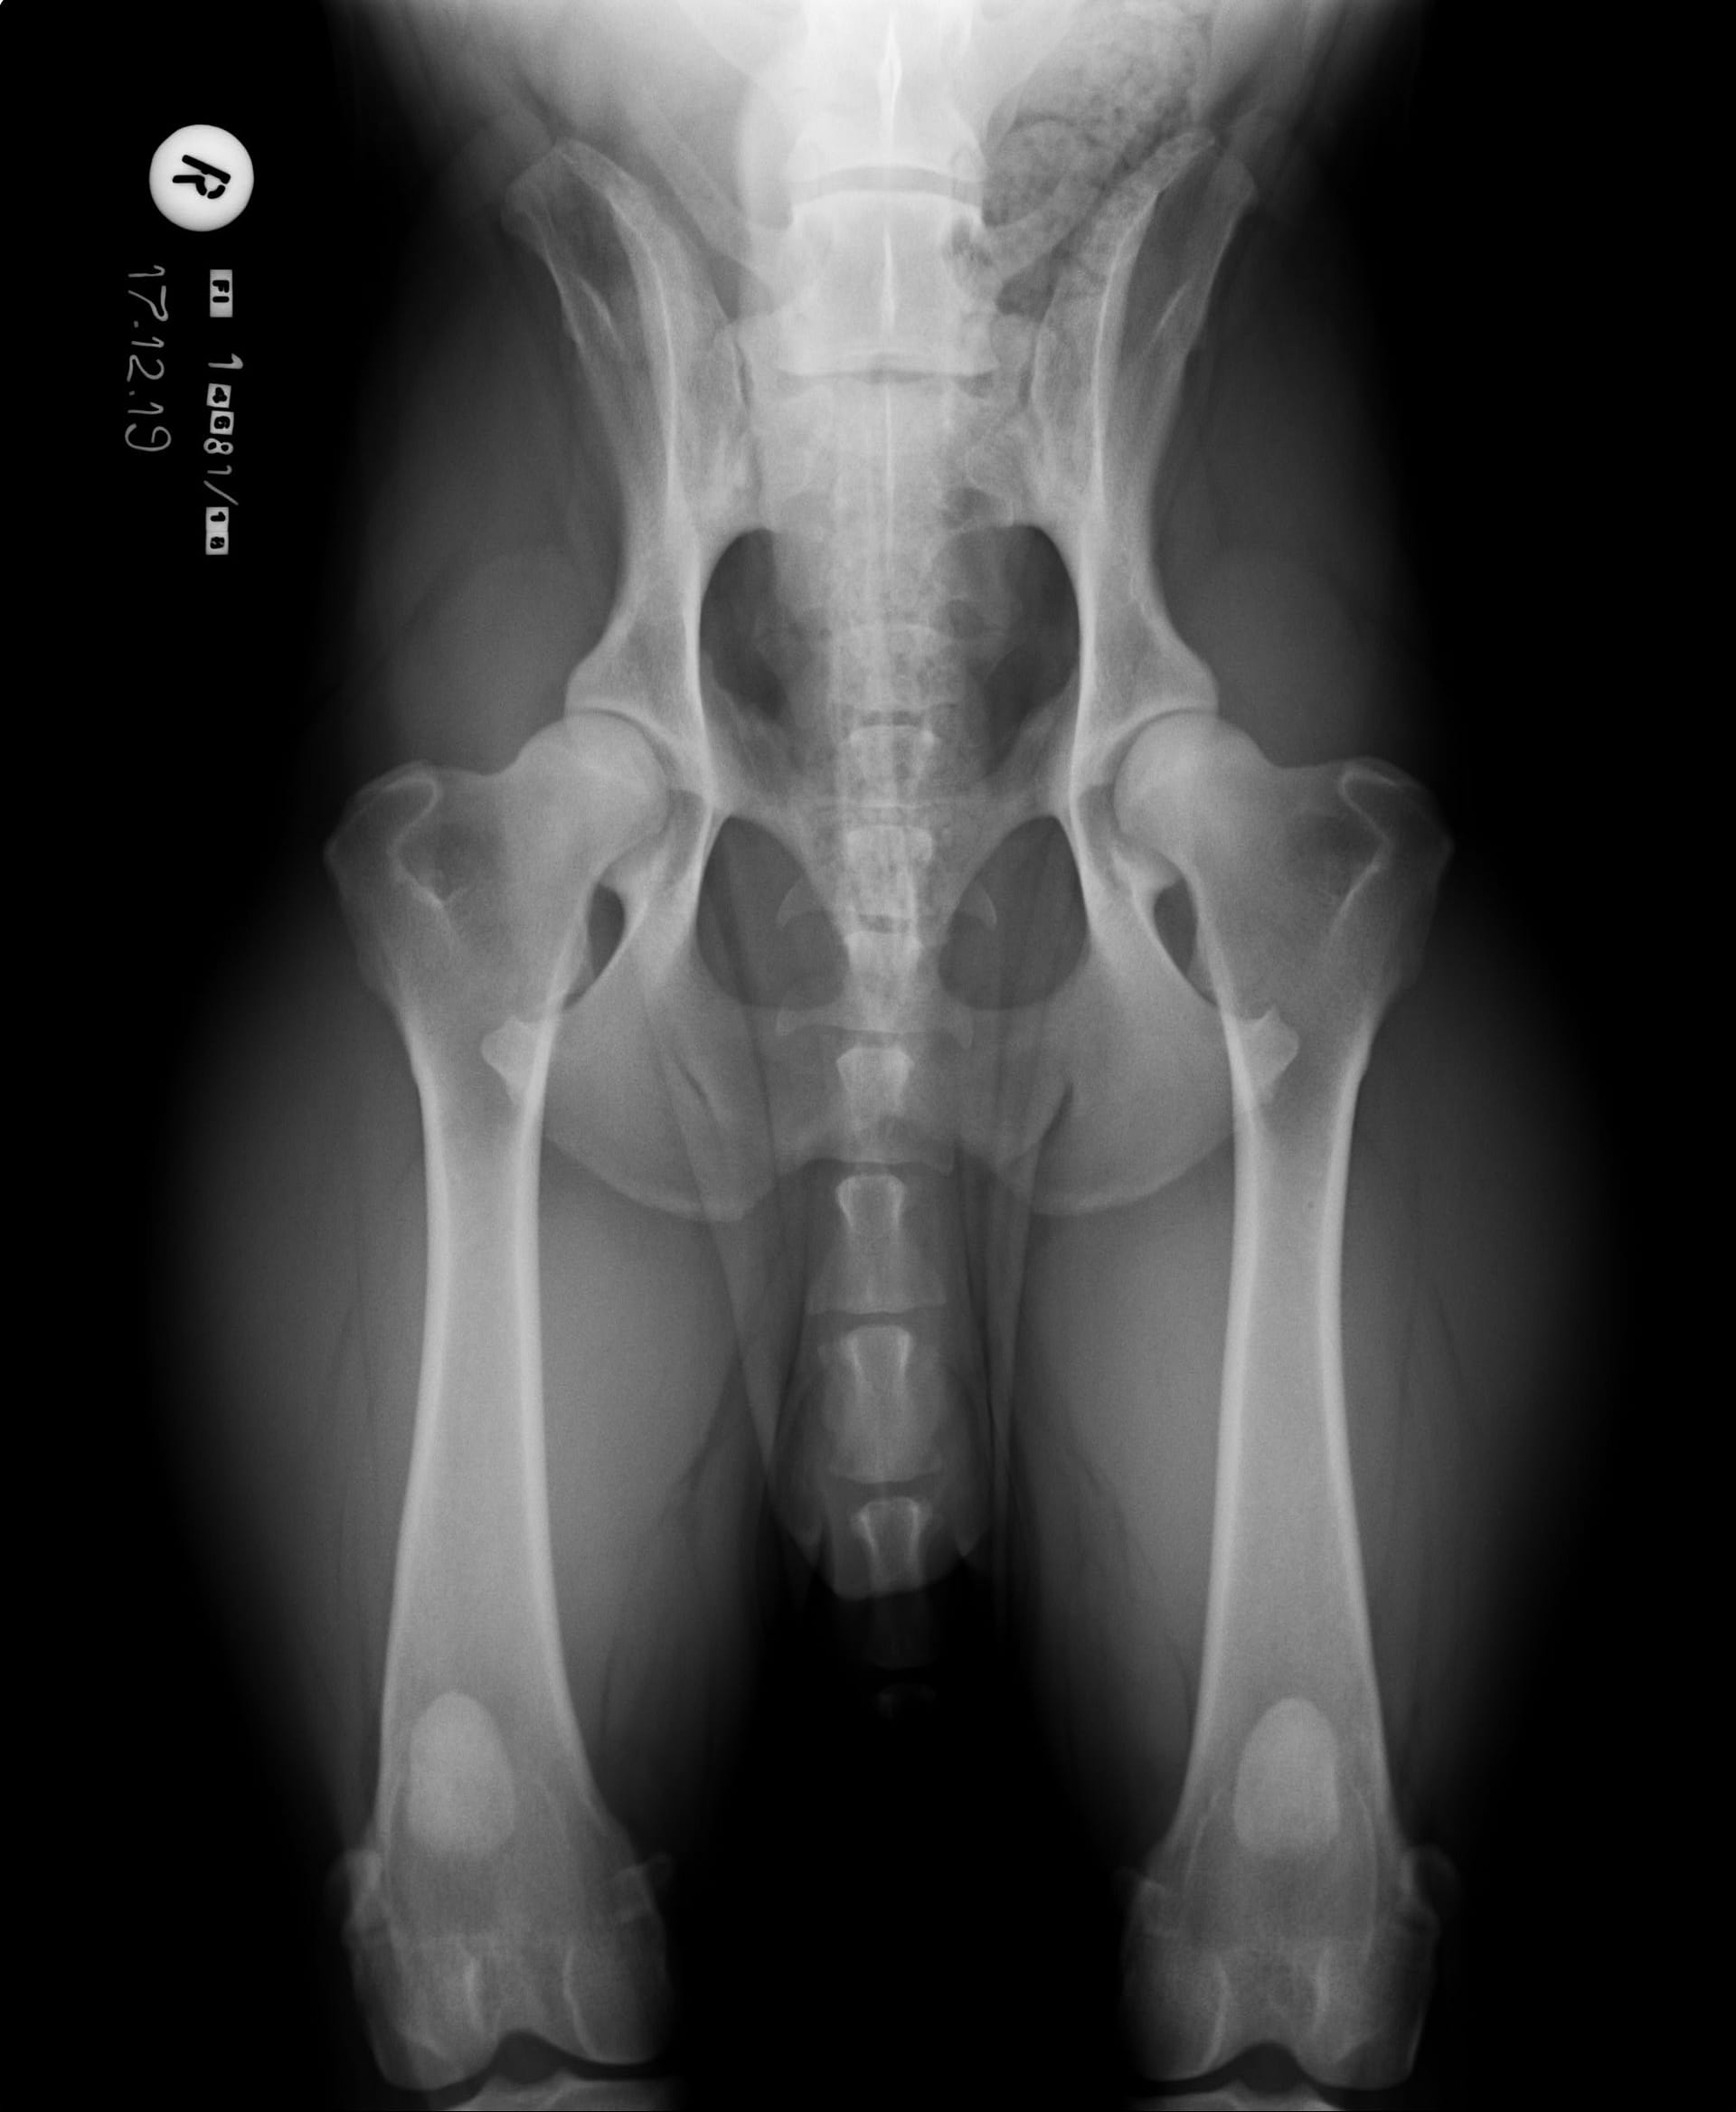

Tähän mennessä Iivo on ollut täysin terve ja Iivo tutkittiin luustoltaan terveeksi joulukuussa 2019. Luonnekuvaukseen (MH, laukausvarma) Iivo osallistui elokuussa 2020.

| Lonkat: | A/A |

| Kyynärät: | 0/0 |